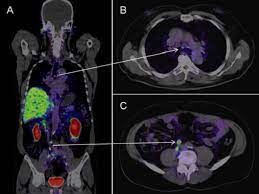

Pet scans also prevent unnecessary surgeries and help suggest which cancer therapies are likely to be most effective for specific tumor types. Because of this high level of chemical activity, cancer cells the combined use of pet scans and ct scans is an effective method for detecting pelvic recurrences of rectal cancer. Cancer cells tend to be more active than normal cells. Pet/ct scans provide significantly more information than ct scans, and are far more reliable when diagnosing cancer. A pet scan works by detecting the energy released by positrons.

Pet Ct In Anal Cancer Indications And Limits Intechopen from www.intechopen.com The scanner detects diseased cells that absorb. Pet scans also prevent unnecessary surgeries and help suggest which cancer therapies are likely to be most effective for specific tumor types. Pet scans use radioactively tagged molecules (or tracers) to image a wide array of molecular processes and when detected by a pet scanner, the tracers help your doctor to see how well your organs and tissues are working. The pet scanner detects signals that are given off from the tracer. It also can let you and your doctors know if cancer treatment is working. Most pet scans use a type of radiolabeled sugar to detect the cancer, as the majority of cancers grow quickly and need sugar for that growth. Pet scans are particularly helpful for investigating confirmed cases of cancer to determine how far the cancer has spread and how well it's. Pet/ct, which is a combination of positron emission tomography (pet) with computerized tomography (ct), is a powerful, essential tool for cancer detection and diagnosis.

In this case, your body position will be very important. Pet scanners work by detecting the radiation given off by a substance injected into your arm called a radiotracer as it collects in different parts of your body. Pet scans, short for positron emission tomography, can detect areas of cancer by obtaining images of the body's cells as they work. It also can let you and your doctors know if cancer treatment is working. The test uses a safe injectable radioactive chemical called a radiotracer and a device called a pet scanner. A pet scan is not specific for cancer. Pet scans use radioactively tagged molecules (or tracers) to image a wide array of molecular processes and when detected by a pet scanner, the tracers help your doctor to see how well your organs and tissues are working. Pet scan is a special type of imaging test in which tracers are injected & are absorbed into organs of body and images are obtained. Nuclear medicine images use a small quantity of a radioactive substance to detect, evaluate, or treat various diseases. Positron emission tomography (pet) imaging or pet scan is a nuclear medicine imaging. With that being said, not all cancers can be detected by pet. Because of this high level of chemical activity, cancer cells the combined use of pet scans and ct scans is an effective method for detecting pelvic recurrences of rectal cancer. Possible risks of a pet scan.

A new test called a psma pet scan makes these tumors easier to spot. Pet scanners work by detecting the radiation given off by a substance injected into your arm called a radiotracer as it collects in different parts of your body. The pet scan detects the concentrated psma tracer, pinpointing these tumors for more effective treatment. Pet/ct scans provide significantly more information than ct scans, and are far more reliable when diagnosing cancer. Pet/ct, which is a combination of positron emission tomography (pet) with computerized tomography (ct), is a powerful, essential tool for cancer detection and diagnosis.